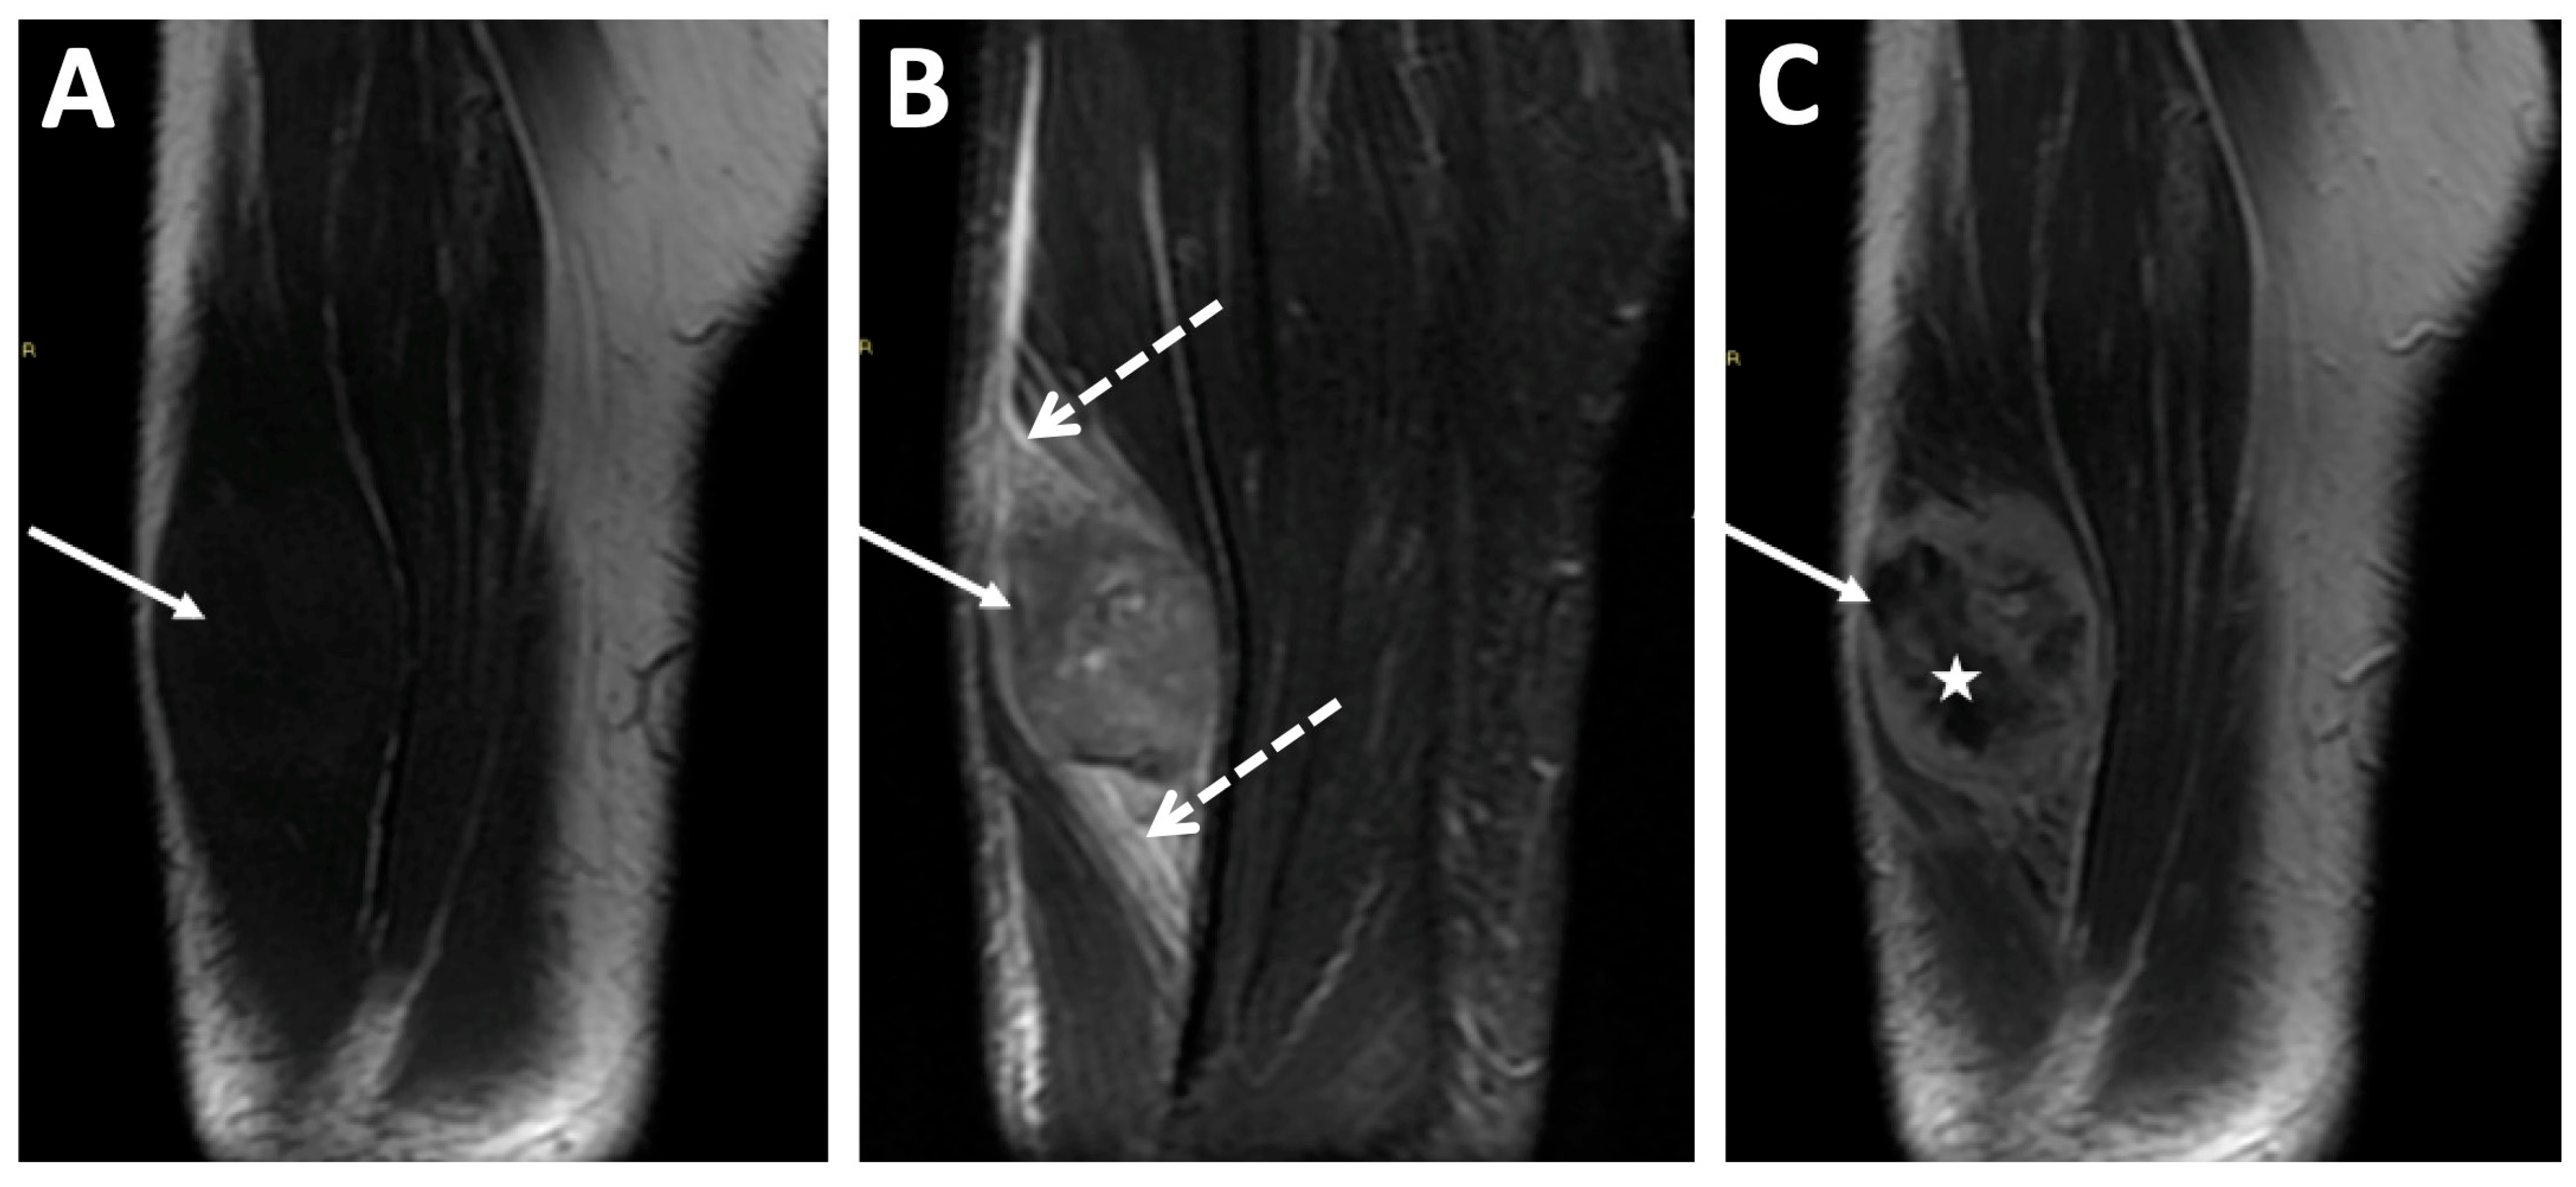

| ESOS | Soft-tissue mass with inhomogeneous contrast enhancement, various degrees of internal necrosis | None | Internal mineralization frequently displayed (60%) |